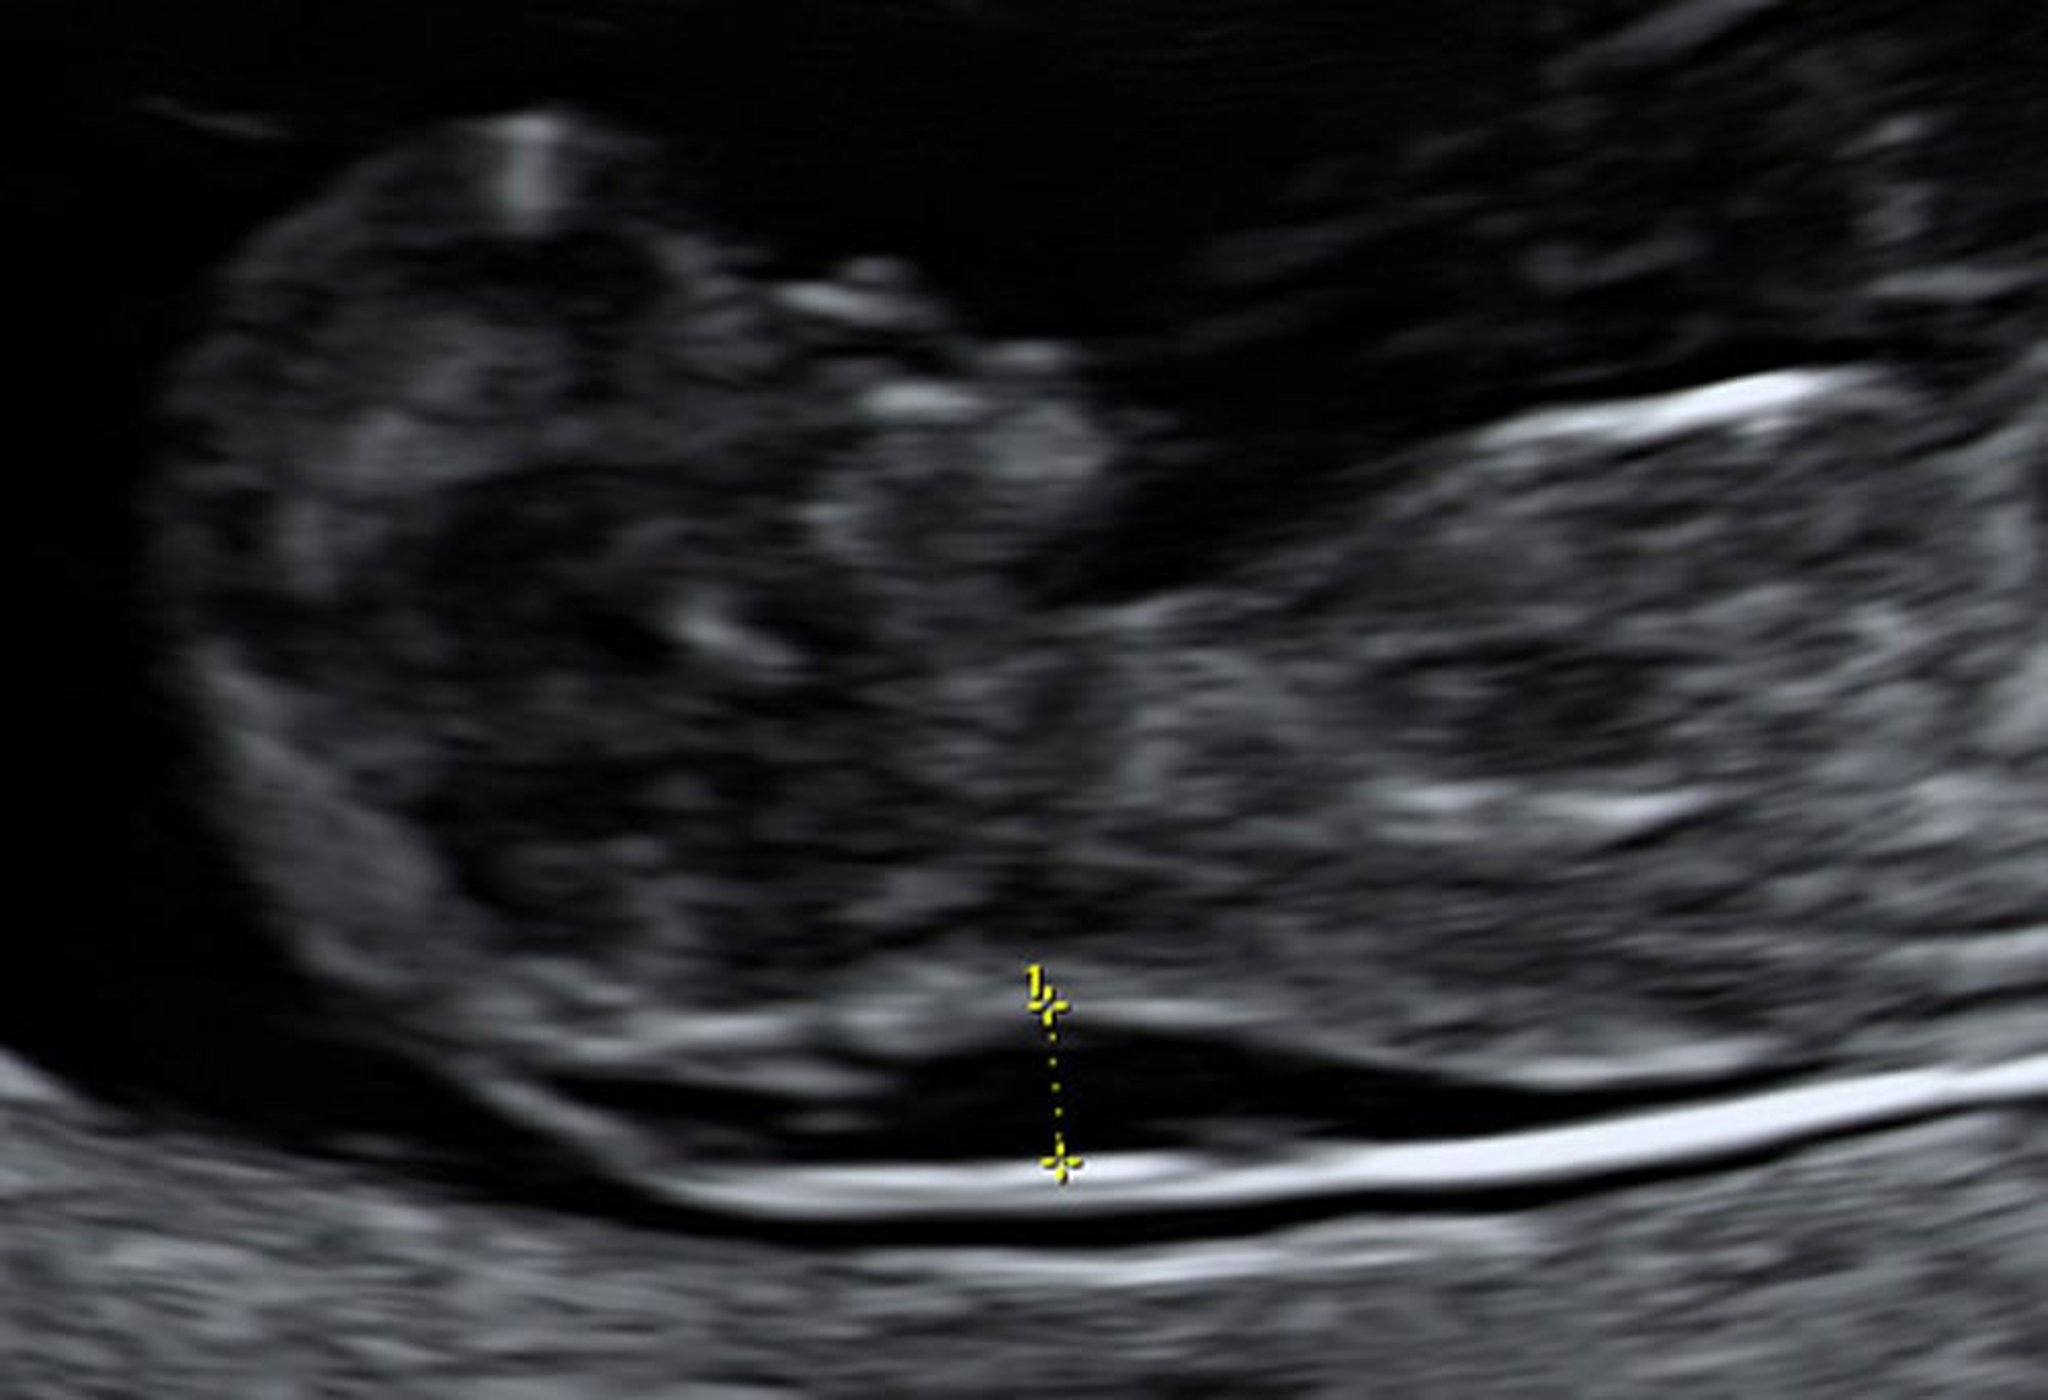

Ultraschalluntersuchung mit vergrößerter Nackentransparenz bei einem Fetus in der 10. Woche

Eine Chorionzottenbiopsie ergab, dass dieser Fetus das Down-Syndrom hatte.

Foto von Jeffrey S. Dungan, MD.